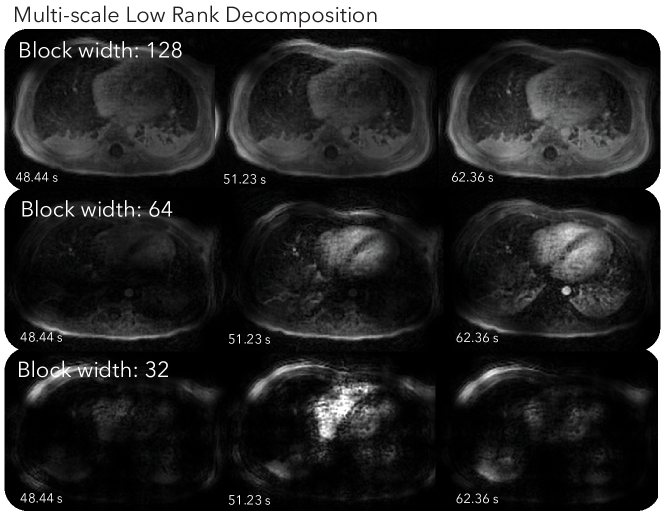

Figure 3 and Supporting Information Video S5 show the corresponding MSLR decomposition. The scale with the 1283-sized blocks mostly shows static background tissues. The scale with the 643-sized blocks depicts mostly contrast enhancements in the heart and aorta, and respiratory motion. The scale with 323-sized blocks displays spatially localized dynamics, such as those in the right ventricle, and oscillates more over time than other scales.